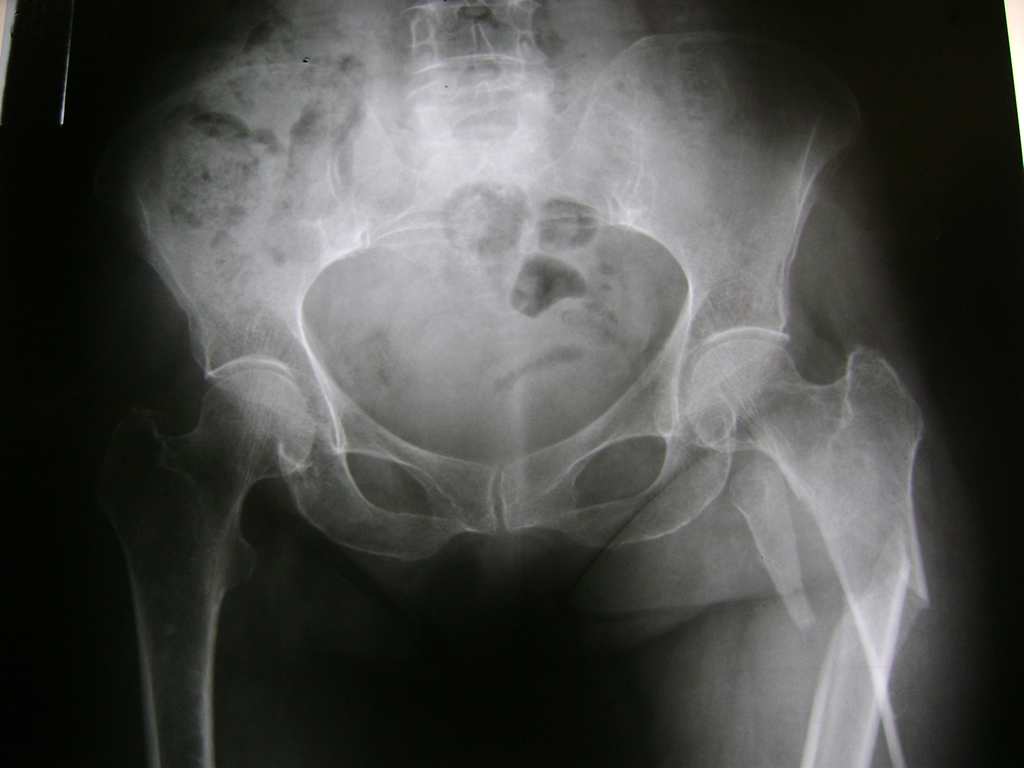

La cirugía de fractura de cadera se realiza para reparar una ruptura en la parte superior del hueso del muslo. Este hueso se denomina fémur.

Es parte de la articulación coxofemoral. Si una fractura de cadera no recibe tratamiento, es posible que deba permanecer en una silla o en la cama.